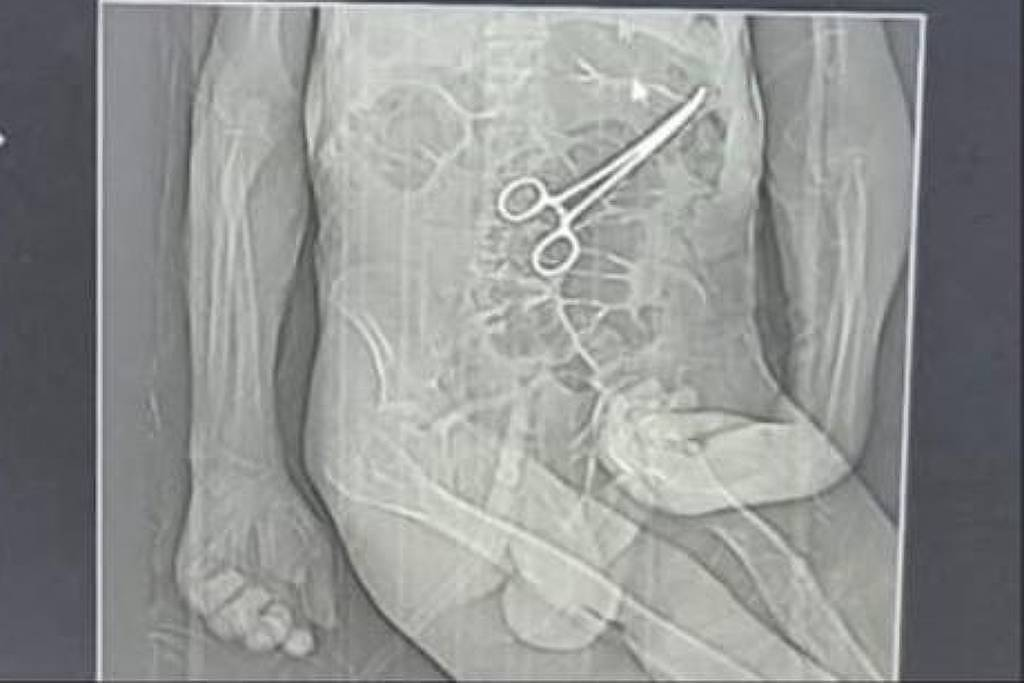

Tomografia usada pela família de Manoel Cardoso de Brito para acusar médicos de hospital de João Pinheiro (MG) de deixar pinça no abdômen do idoso após cirurgia – Reprodução

A família de um aposentado que morreu na véspera do último Natal em João Pinheiro, no noroeste de Minas Gerais, acusa médicos do hospital municipal de esquecerem uma pinça no abdômen do idoso durante uma cirurgia feita semanas antes do óbito.

Após a cirurgia, o paciente voltou a apresentar sintomas graves, o que levou à realização de novos exames. Nesse momento, uma tomografia identificou, segundo a secretaria, “um corpo estranho na cavidade abdominal”.

Os parentes também afirmam que só souberam do que de fato havia ocorrido por meio de uma reportagem de uma rádio local, quando tomaram conhecimento da imagem de uma tomografia indicando uma pinça no abdômen de Manoel.